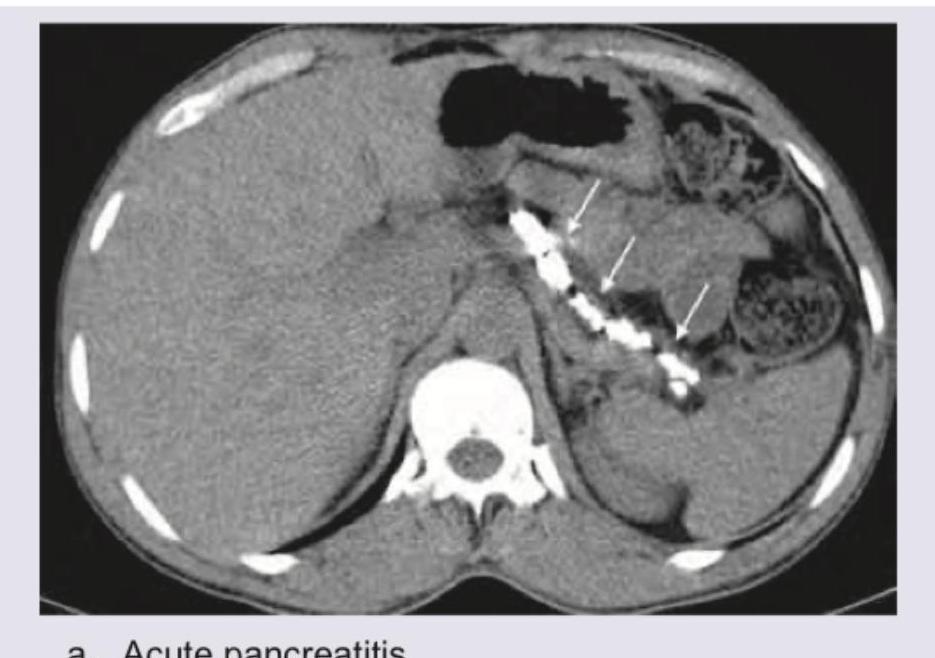

Explanation: ***Acute pancreatitis*** - The image shows an **enlarged, edematous pancreas** with surrounding **stranding of the peripancreatic fat**, indicated by the white arrows and suggesting inflammation. - There is also evidence of **fluid collection** adjacent to the pancreas, a common finding in acute pancreatitis. *Chronic pancreatitis* - Chronic pancreatitis typically presents with pancreatic **atrophy**, **calcifications** within the parenchyma and ducts, and **ductal dilation**. - While calcifications are present, the primary findings of a swollen pancreas and peripancreatic edema are more indicative of an acute process. *Pancreatic divisum* - Pancreatic divisum is a **congenital anomaly** where the dorsal and ventral pancreatic ducts fail to fuse, and it is a predisposing factor for pancreatitis, but the image shows findings of an inflammatory process rather than an anatomical variant. - The image exhibits signs of inflammation and fluid collection, not the distinct ductal anatomy of pancreatic divisum itself. *Artefact* - Artefacts on a CT scan can include **beam hardening**, **motion artefacts**, or **streak artefacts**, which typically appear as streaks, distorted images, or areas of abnormal signal. - The observed features—pancreatic enlargement, peripancreatic fat stranding, and fluid collection—are clear anatomical and pathological changes, not image anomalies.